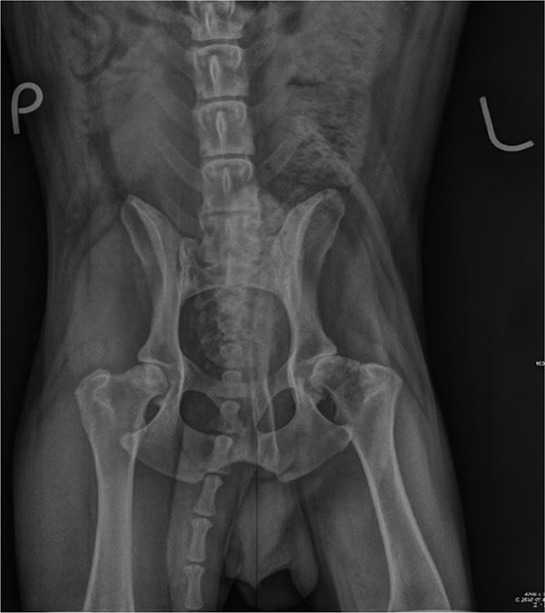

The most common orthopaedic developmental disease in dogs is hip dysplasia. This condition results in coxofemoral laxity due to incongruity and lack of stabilisation of the joint by the soft tissues. Currently, there is no therapeutic plan to correct hip dysplasia without surgical intervention at a very early age. The goal of the non-surgical treatment is to relieve pain and stiffness and to increase the muscle strength, usually through hydrotherapy and the beneficial physical properties of water. Recently, there has been growing interest in regenerative medicine, which involves the use of mesenchymal stem cells (MSCs) and their products to alleviate the characteristic clinical symptoms of osteoarthritis (OA). In vivo studies with canine MSCs have shown that an intra-articular injection of MSCs into cartilage lesions leads to the excellent regeneration of the hyaline cartilage. Regenerative medicine has undergone rapid development in recent years thanks to new therapies based on the application and combination of innovative biomaterials. One of the first known regenerative methods to be used in clinical practice was platelet-rich plasma (PRP). This review summarises the use and potential of MSCs and PRP, including their in vitro properties, their therapeutic effects in the treatment of cartilage lesions in preclinical in vivo studies, their clinical efficacy in the treatment of naturally occurring OA in dogs, and the current limitations of the studies.